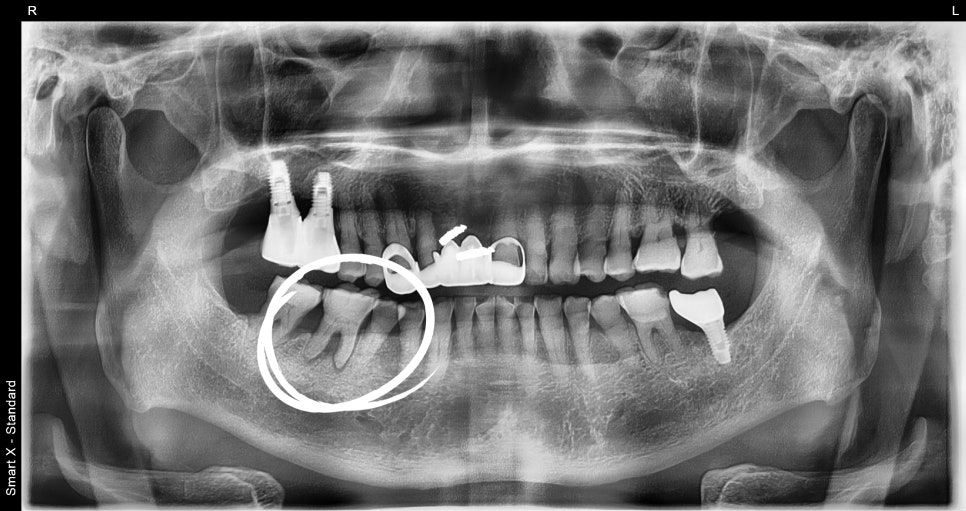

but also by gum inflammation or periodontal disease. In one case, a 70-year-old male patient visited the clinic with pain in the lower right

molar, and the examination revealed both periodontitis and

gum inflammation.

In this patient’s case as well, tartar removal and

periodontal treatment were performed first.

After molar extraction, implant placement is performed.

At this stage, what matters most is the condition of the bone.

Because the molar area often lacks sufficient bone, bone grafting is often performed together.

In this patient’s case as well,

guided bone regeneration and allogeneic bone grafting were performed together.